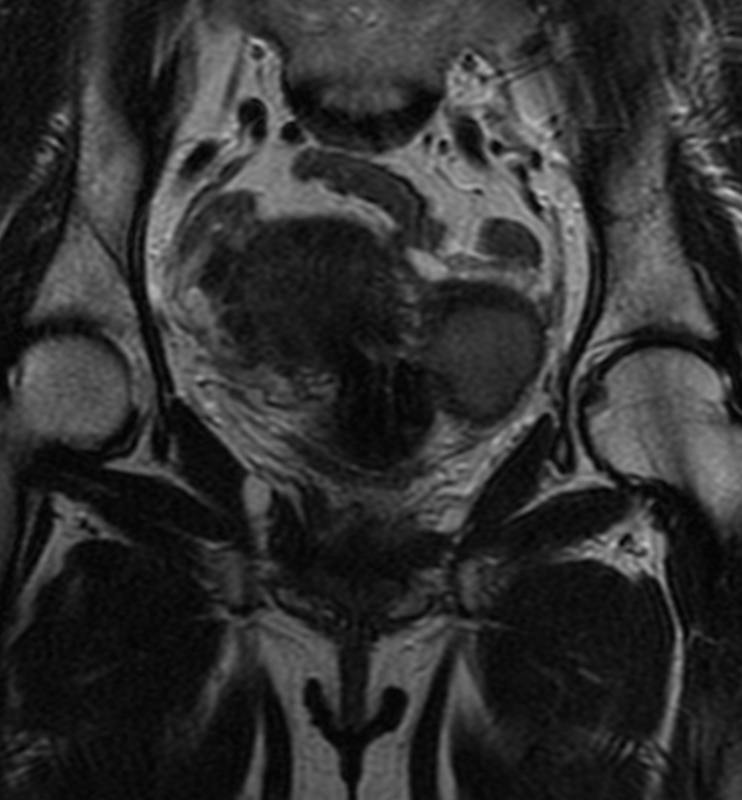

Дивертикул матки у женщины 45 лет.

Дивертикул матки - это редкий врожденный порок развития, вызванный аномальным слиянием мюллеровых протоков.

Диагноз дивертикула матки затруднен, и его часто неправильно диагностируют как другую аномалию Мюллерова протока (например, кровь в рудиментарном роге матки), миому матки с дегенерацией, эндометриому или геморрагическую кисту яичника.

Встречается так редко, что я, вот, первый раз сам увидел, и то, спасибо коллеге из Алма-Аты.